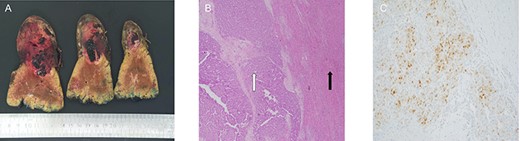

(A) macroscopic specimen demonstrating slices through a haemorrhagic lesion with normal liver parenchyma; (B) images demonstrating liver with intact architecture (black arrow) with HCC (white arrow) and (C) patchy nuclear staining with arginase-1 immunohistochemical stain.

Histopathological assessment revealed an 85-mm moderately differentiated HCC with evidence of vascular invasion that was completely excised with a 20-mm clear margin [TNM Staging (AJCC 8th edition): pT2] (Fig. 3). The patient’s recovery post-procedure was routine with transfer back to the rural hospital 13 days post-liver resection.